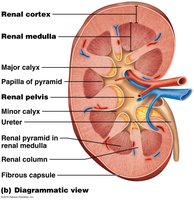

Renal Cortex: Outer region containing most nephrons.

Renal Medulla: Inner region with renal pyramids and loops of Henle.

Renal Pelvis: Funnel-shaped structure collecting urine into the ureter.

Renal Corpuscle: Includes the glomerulus (fenestrated capillary bed) and Bowman’s capsule (with podocytes forming filtration slits).

Renal Tubules: Proximal convoluted tubule (PCT), loop of Henle, distal convoluted tubule (DCT), and collecting duct.